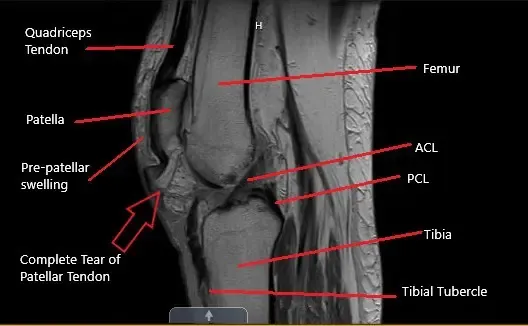

MRI of the knee in the sagittal section showing a complete tear of the patellar tendon

MRI of the left knee suggested a full-thickness midsubstance tear of the patellar tendon with approximately 1.7 cm fluid gap and associated patella Alta. There was diffuse infiltration/edema within the infrapatellar and prepatellar fat. The patient is a retired banker and had an active lifestyle before the injury.